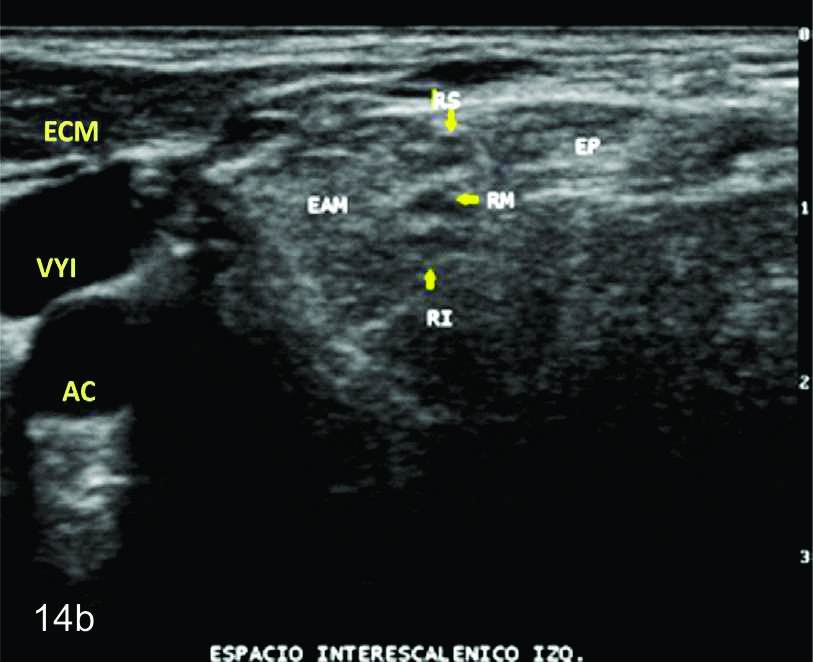

En el miembro superior predominan sobre el plexo braquial aunque pueden afectar otros troncos nerviosos como el mediano, radial o cubital. Estas últimas son generalmente secundarias a fracturas, lesiones penetrantes o iatrogénicas. (Fig. 14).

Figura 14 a y b

Lesión traumática del plexo braquial luego de accidente en moto.

A y B- cortes comparativos transversales al plexo braquial al nivel del espacio interescalénico (A-derecho patológico y B-izquierdo sano), se demuestra la asimetría de las estructuras del plexo. RS- tronco superior, RM-tronco medio, RI-tronco inferior, EP- músculo escaleno anterior, EAM-músculos escalenos medio y anterior.